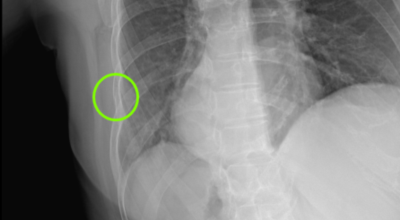

일반인이 근육통과 금이 간 경우의 차이는 거의 판별하기 힘들어요. 갈비뼈라고 하는 부분이 눈에 보이도록 붓는 것도 아니고, 멍이 들어서 아픈것도 아니기 때문이지요. 가장 정확하게 판별하는 방법은 엑스레이를 찍는 방법이지요.